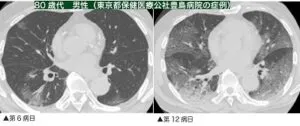

画像所見:胸部CT検査では、症状が無くても異常を認めることがあり、

武漢市における81例の患者CT所見のまとめでは、79%に両側の陰影を認め、54%は肺野末梢に分布していた。すべての肺野に異常陰影を認めうるが、右下葉に多い傾向を認めた。

発症から1~3週間の経過でスリガラス陰影から浸潤影に変化する。第14秒実頃にピークとなることが多く、CT画像所見と肺酸素化能はしばしば乖離する。